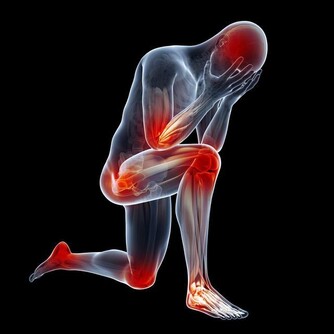

在我國,大約85%的下肢截肢是糖尿病足引起的。

糖尿病引起的下肢血管病變和合併感染,是引起糖尿病足最主要的原因。

一方面,糖尿病性下肢血管病變,會導致足部局部缺血缺氧,延遲傷口癒合;

另一方面,高血糖使患者自身免疫功能下降,對感染的防禦能力降低,有利於細菌的繁殖。

因此,各位糖友需要注意,保護自己的雙足,避免受傷和乾擾,從而引發糖尿病足。